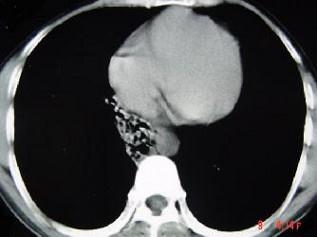

问题 男,26岁,肺部感染后反复咳嗽咳痰一月,CT检查如图,最可能的诊断为 ( )

选项 A、支气管扩张并感染 B、肺癌 C、右下肺隔离症并感染 D、肺部感染 E、支气管囊肿并感染

答案 C